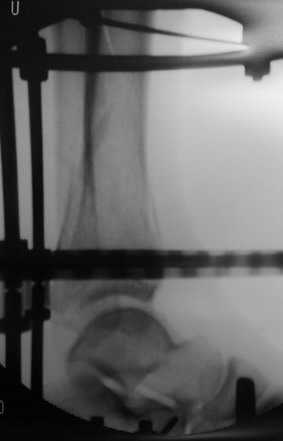

На мой взгляд оптимальным для такого перелома является аппарат Илизарова, который позволяет:

3. Ранняя разработка сустава в аппарате

4. Частичная нагрузка с первых дней после операции

Пример - довольно похожий перелом, оперированный в первые 8 часов после аварии у 40-летнего больного, страдающего тяжёлым сахарным диабетом 1 типа.